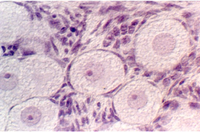

- Testes

- Efferent ducts

- Epididymus